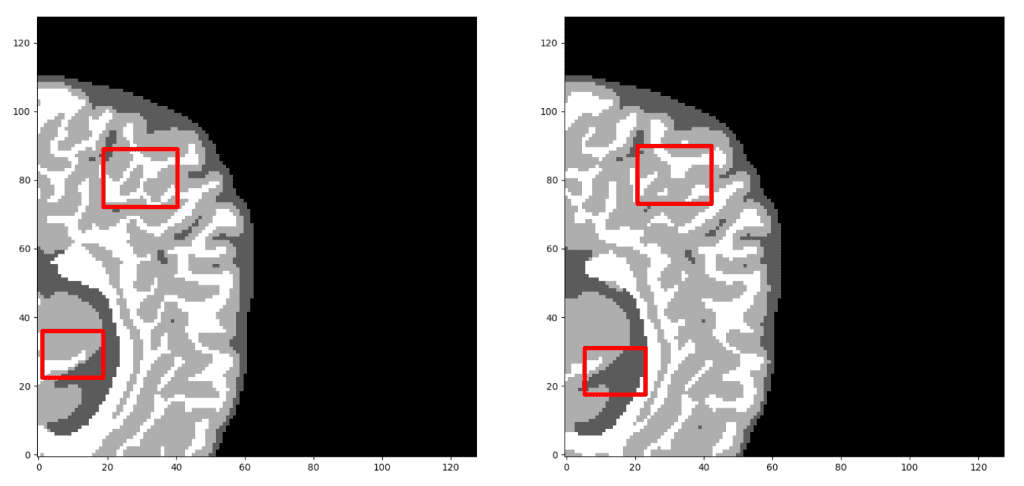

该模型在子卷的验证集中达到了大约 93% 的骰子系数分数。最后但同样重要的是,让我们看看验证集中 3D-Unet 的一些可视化预测。尽管预测是 3D 体积,但我们在这里只展示一个代表性切片。通过获取 MRI 的多个子体积,可以将它们组合起来形成完整的 3D MRI 分割。请注意,我们使用子卷采样的事实是数据增强。

我们的预测 VS 基本事实。您认为哪个预测是基本事实?仔细看看再做决定!需要注意的是,我们在这里只展示了中轴切片,但预测是一个 3D 体积。可以观察到,该网络完美地预测了空气体素,但难以区分组织边界。但是,让我们再次检查以找出真正的那个!

现在,我相信您可以区分基本事实。如果不确定,请查看文章末尾:)